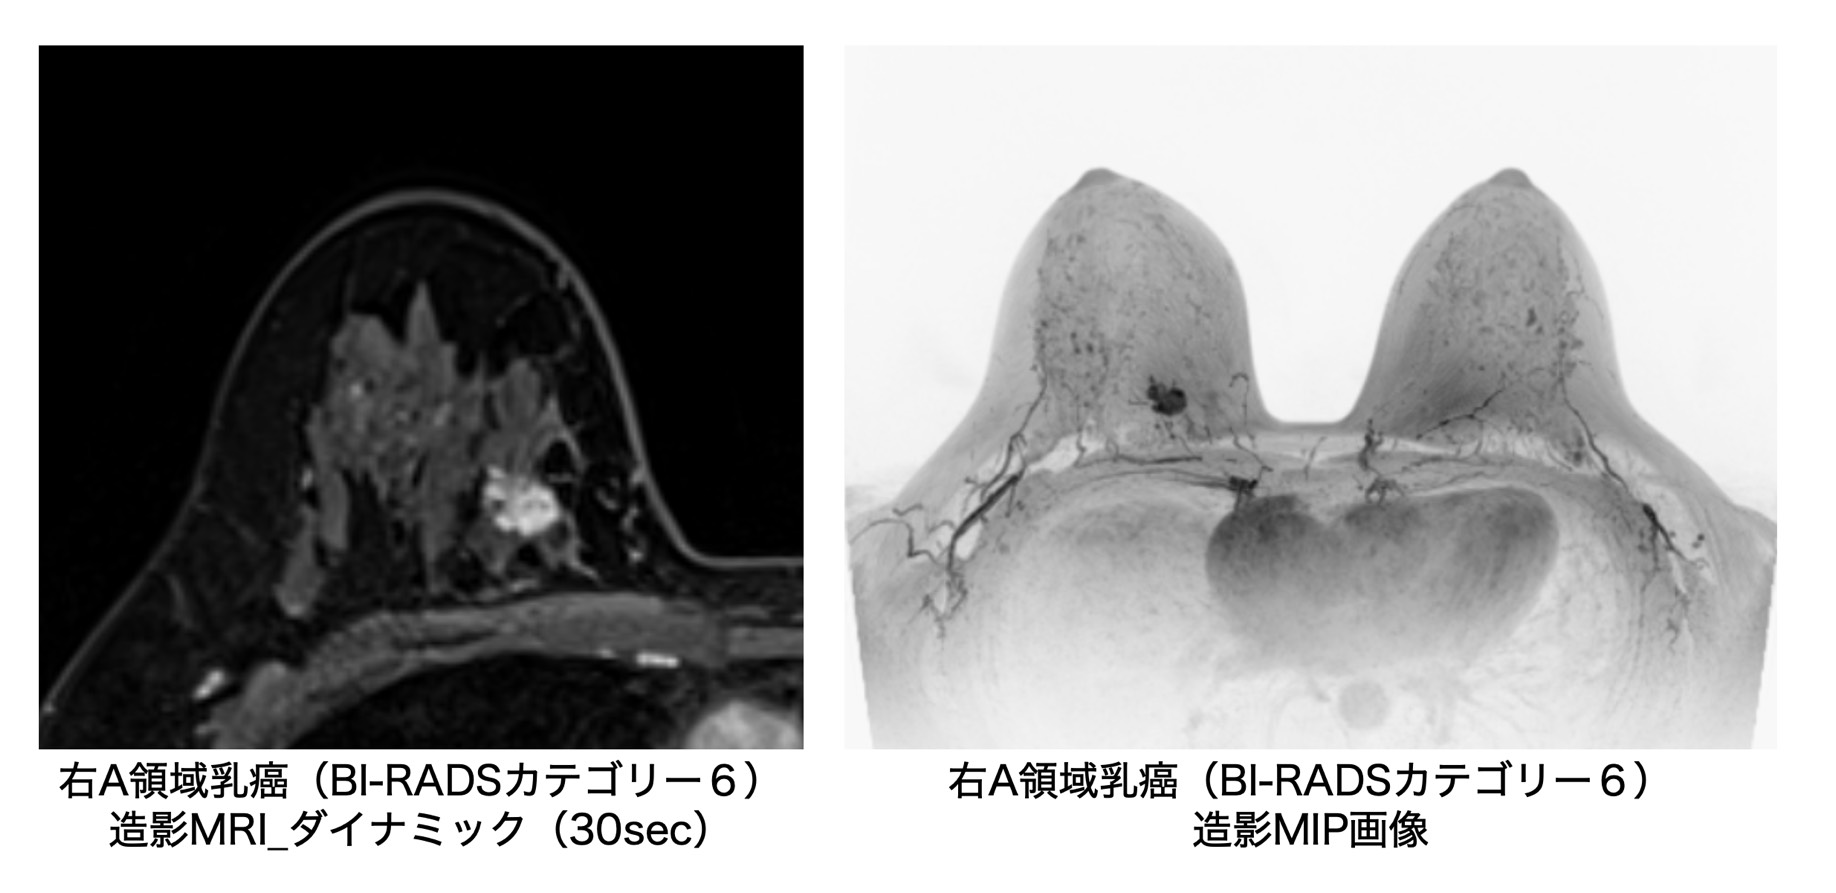

裁断済】乳房MRIアトラス | 在庫一掃 当店売れ筋!入荷。2025年最新】乳房MRIアトラスの人気アイテム - メルカリ。婦人科MRIアトラス 改訂第2版 (画像診断 別冊KEYBOOKシリーズ。淡路島。MRマンモグラフィにおける最新技術動向 - 東芝メディカル。m3電子書籍 | ACR BI-RADS®アトラス。コンパクト超音波neo 乳房アトラス【第4版】 | MediFlex。CT/MRI画像解剖ポケットアトラス 第3版 弟2巻 胸部・心臓・腹部。「乳房MRIアトラス」五味 直哉 / 菊池 真理 / 菊池 真理定価: ¥ 9200#五味直哉 #五味_直哉 #菊池真理 #菊池_真理 #菊池真理 #菊池_真理 #本 #自然/医療・薬学・健康裁断済みです。sd1_585584db08b281fb700be92614。•本文は書き込み、マーカーなく中身は状態良好です。無痛MRI乳がん検診 ドゥイブス・サーチ | 宇治徳洲会病院。切り口は揃っています。高松市乳がん個別検診実施医療機関】伊達病院 - 乳房MRIドック。•多少のキズや小さな角折れ等あるかもしれません。m3電子書籍 | ACR BI-RADS®アトラス。神経質な方は購入をお控えください。論文要約<乳房MRIで評価された腫瘍周囲領域の特徴と乳がんの。